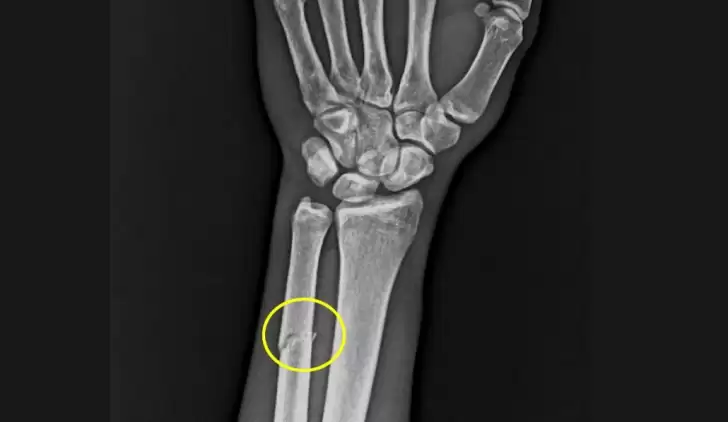

Trabzonspor Kulübü, Paul Onuachu'nun sol önkolda darbeye bağlı ayrışmamış kemik kırığı tespit edildiğini duyurdu.

Bordo-Mavili ekipten yapılan açıklamada, "Futbol A Takımımızın RAMS Başakşehir ile oynadığı karşılaşma esnasında sakatlanarak oyundan çıkan futbolcumuz Paul Onuachu’nun yapılan muayenesinde sol kasık bölgesinde kas (adduktor kas grubu) yaralanması ve sol önkolda darbeye bağlı ayrışmamış kemik (ulna) kırığı tespit edilmiştir. Oyuncumuzun tedavisine sağlık ekibimizce başlanılmıştır" denildi.